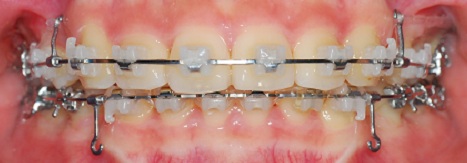

(13번째 교정 일기에서의 치아 상태)

예전에는 앞니가 아랫니를 많이 덮었는데 지금은 윗 니와 아랫니가 많이 보입니다.

(19번째 교정 일기에서의 치아 상태)

많이 달라졌죠?